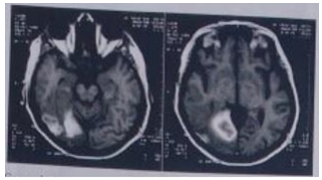

Paciente de 27 anos de idade foi levado ao pronto-socorro em razão de perda progressiva da capacidade de realizar atividades laborais e domiciliares em contexto de meses, acompanhada por sonolência e cefaleia constantes. Foi realizada tomografia computadorizada em regime de urgência, com laudo ainda não disponível, representada a seguir (conforme imagem do caderno de questões). Com base nas informações apresentadas, assinale a alternativa que indica, respectivamente, a melhor hipótese diagnóstica para esse caso e um exame que a reforçaria: